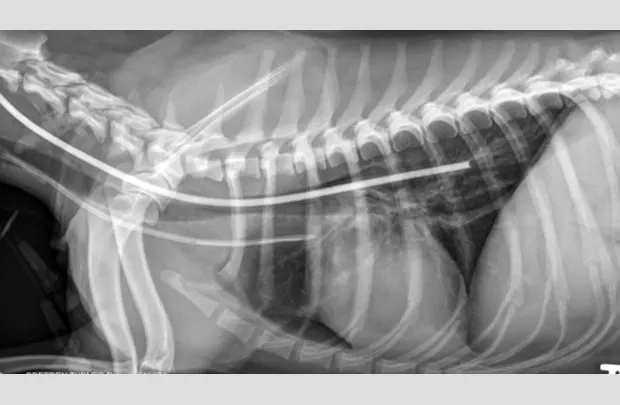

Ensure the tube is properly positioned via lateral radiography (A).

If placement is uncertain, infuse a small amount of nonionic contrast material to differentiate the esophagostomy tube from the endotracheal tube or jugular catheter (B).

FIGURE A